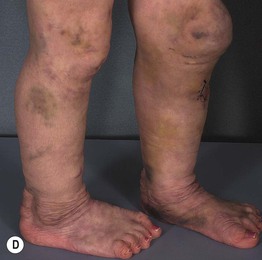

Fig. 80.1 Clinical features of Ehlers–Danlos syndrome (EDS). Patients with classic EDS demonstrating joint hypermobility (A), hyperextensible skin (B), and a widened atrophic scar (C). Extensive bruising on the shins in a patient with dermatosparaxis (D); similar changes can be seen in vascular EDS. D, Courtesy, Julie V. Schaffer, MD.

• Manifestations of cutaneous fragility include easy bruising (sometimes leading to suspicion of a bleeding disorder; see Fig. 80.1D) and gaping, ‘fish-mouth’ wounds from minor trauma that heal with widened, atrophic scars (see Fig. 80.1C); additional findings may include smooth velvety skin, molluscoid pseudotumors (fleshy nodules in sites of repetitive trauma), subcutaneous spheroids over bony prominences (small, hard nodules that represent calcified fat lobules), piezogenic papules (see Chapter 82), and elastosis perforans serpiginosa (see Chapter 79).